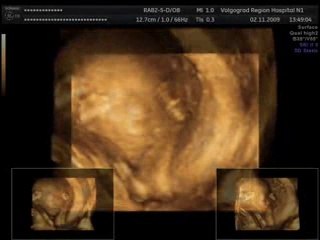

Беременность 2 недели(2 неделя беременности)